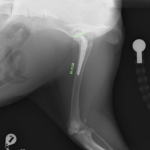

術後X線評価ではインプラント設置は良好。

カップは寛骨臼内側壁に適切に接触し、前後柱間で良好に中心化されています。

ステムは髄腔中央に位置し、内側皮質との接触も良好です。インターロッキングスクリュー固定も適切で、安定した初期固定強度が得られています。

Angle of Lateral Opening (ALO):約45°

Retroversion:約30°

True stem anteversion:約25°